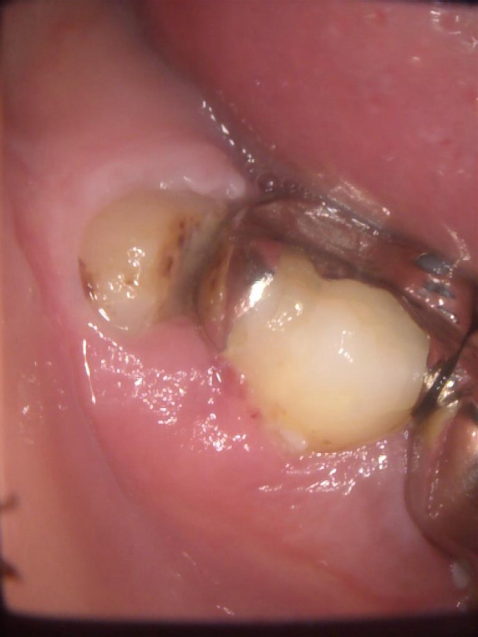

2.親知らずが虫歯になると、その手前の歯も虫歯になる可能性があります

一番右奥の親知らずは良く磨けず、虫歯になることが多いのです。早く抜いて、前の歯が虫歯にならないようにしなければなりません。

親知らずが横(水平)に生えている写真です。隣の歯との隙間は歯磨きすることは出来ません。放っておくと、次の写真の様になります。

左の親知らずは、大事な一本前の歯を虫歯にし、さらに周りの骨を溶かしています。こうなってからでは遅すぎてしまいます。

左端の歯が親知らずです。ブラッシングが難しく、沢山磨き残しがあります。手前の歯も虫歯になっています。